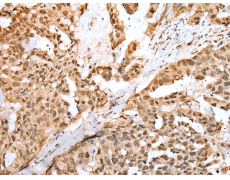

IHC positive control: |

Human breast cancer and human thyroid cancer |

IHC Recommend dilution: |

25-100 |